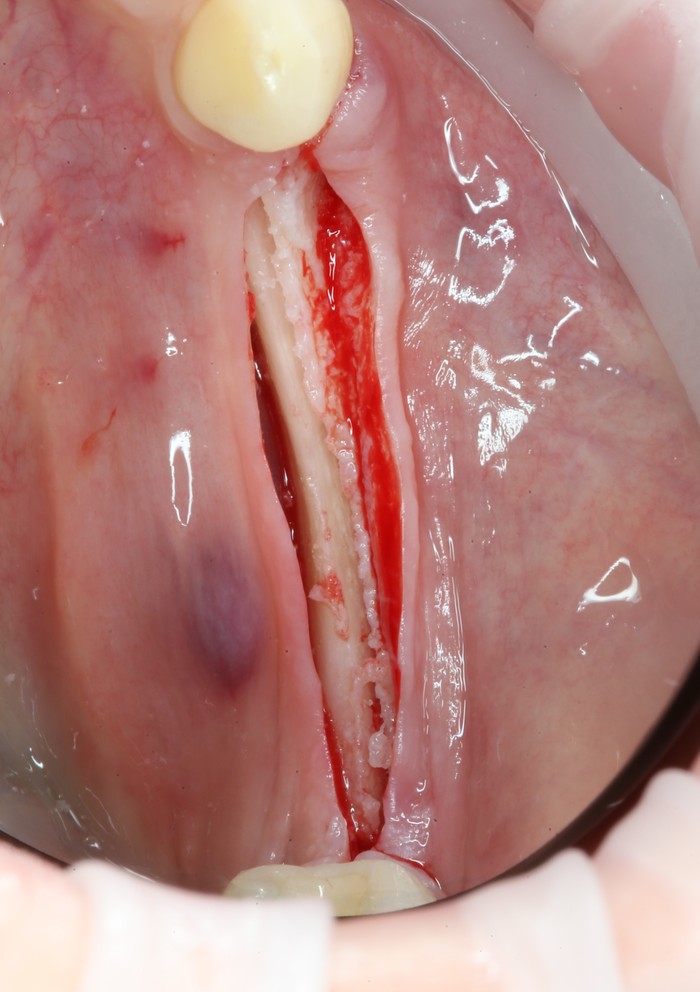

Ниже будут представлены фотографии, сделанные во время приема! С видами зубов, дёсен, крови и расчлененки. Слабонервных прошу отказаться от прочтения данной статьи!!!

В связи с тем, что Руслан приезжает из другого города, первым делом я провел удаление всех зубов, которые невозможно было сохранить. Потому как часики тикают, а заживление после удаления занимает около 2 - 3 месяцев.

Уже на следующий день была запланирована имплантация.